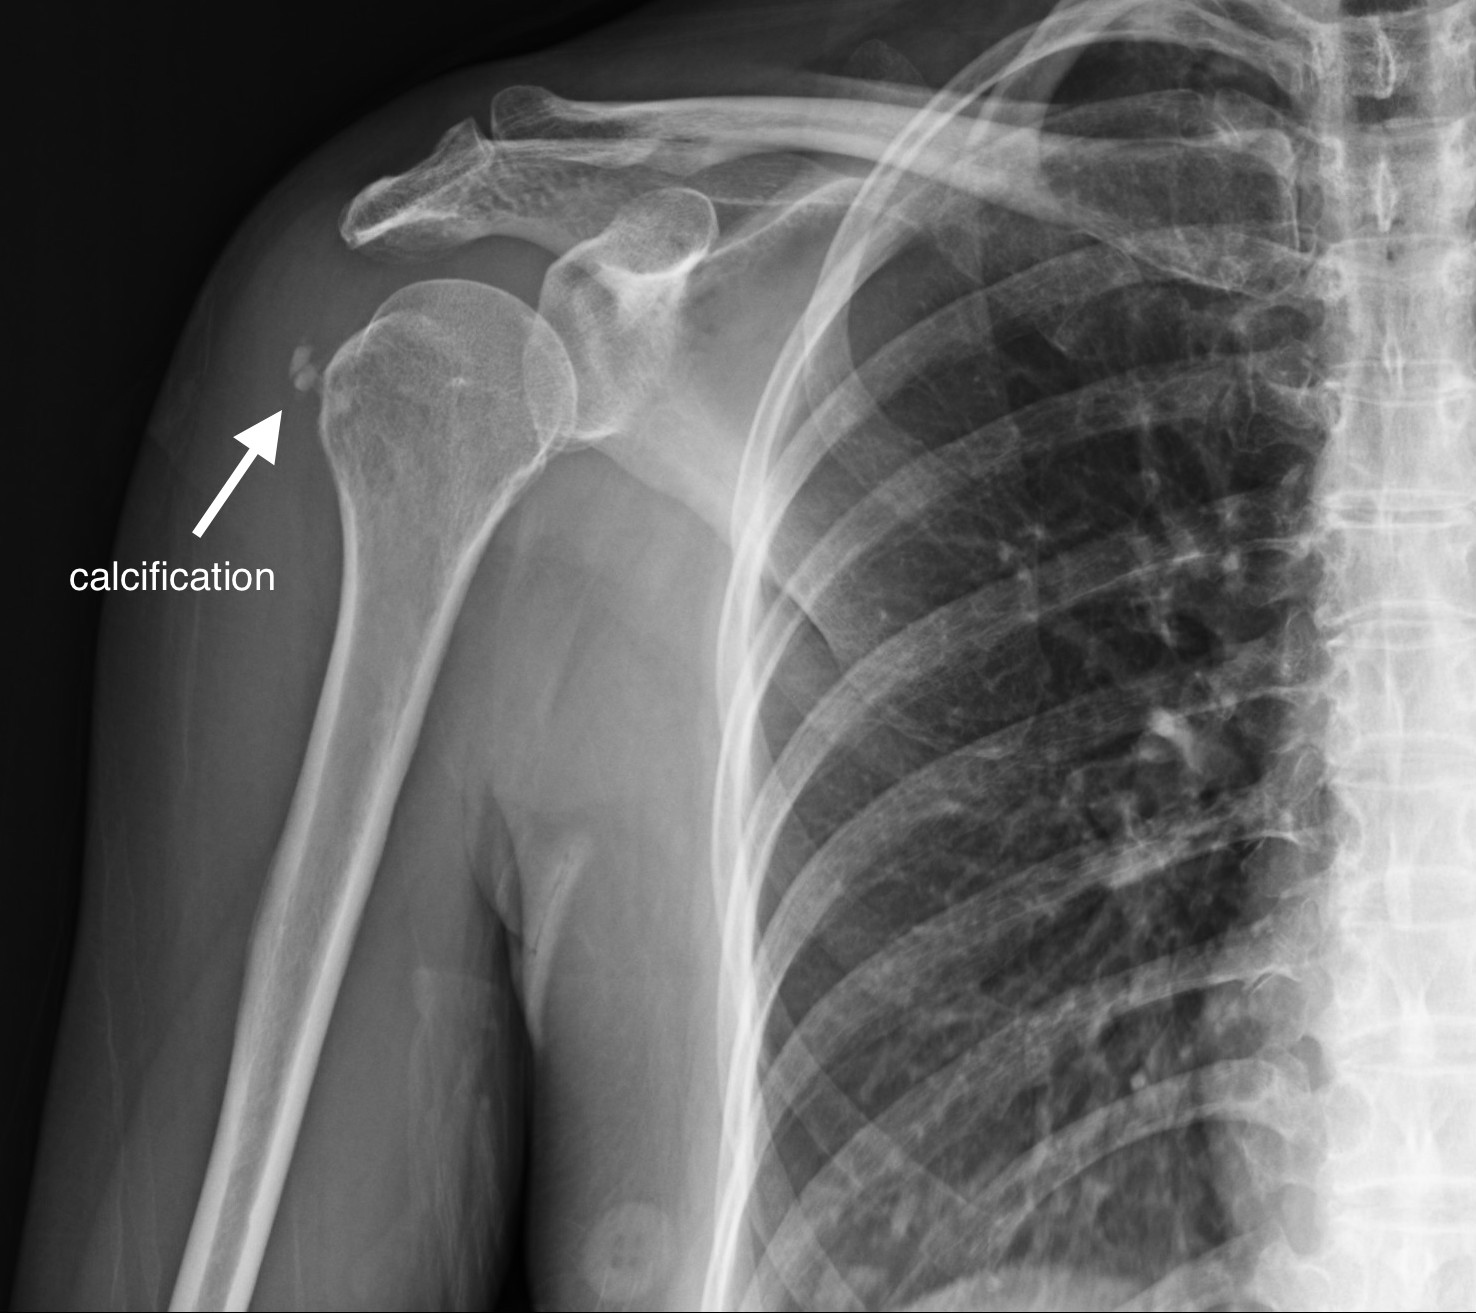

個案56歲女性,右肩外側疼痛4天。無明顯紅腫。生命徵象穩定,急診就診前一天有些微發燒,理學檢查右肩外側一處明顯壓痛,右上臂無法上抬。超音波影像上看到肩關節少量積液(影片8、影片9),但主要疼痛部位在棘上肌腱上的鈣化病變 (圖片6、圖片7)。在超音波導引下我們為該患者進行治療 (影片10),患部疼痛立即得到緩解後自急診出院,安排後續復健科追蹤。

圖片656歲女性,右肩疼痛數日。肩部X光可見鈣化點